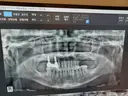

상담원분이 친절하시고 너무 좋았어요! 임플란트 어디서 해야하나 많이 고민했는데 가격도 저렴하니 좋더라구요~ 엘베가 느린건지 타는 사람인지 많은건지 모르겠지만 병원 들어갈때 오래 걸리는 느낌이라 더 긴장되고ㅜㅜ 임플란트가 처음이라 너무 걱정됐는데 괜한 걱정했네요🤭 원장님이랑 간호사분들 너무 친절하셨어요! 과잉진료 이런것도 전혀 없으시구 꼼꼼하니 잘된것 같아서 만족합니다❤️🔥